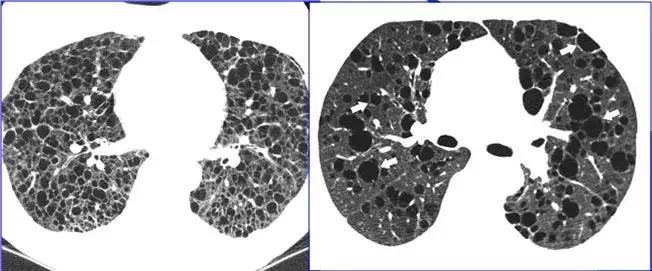

在HRCT上,由于气道疾病或肺血管性疾病引起相邻的肺区血液灌注上的差别而出现的不均匀肺密度区,称马赛克/镶嵌性灌注。常见于造成局部气体滞留或肺实质通气不良疾病中 。

HRCT示略高密度磨玻璃密度影和低密度马赛克灌注区

由于气体储留引起的马赛克灌注

小气道病变引起两侧肺的马赛克灌注

小气道病变引起两侧肺的气体潴留